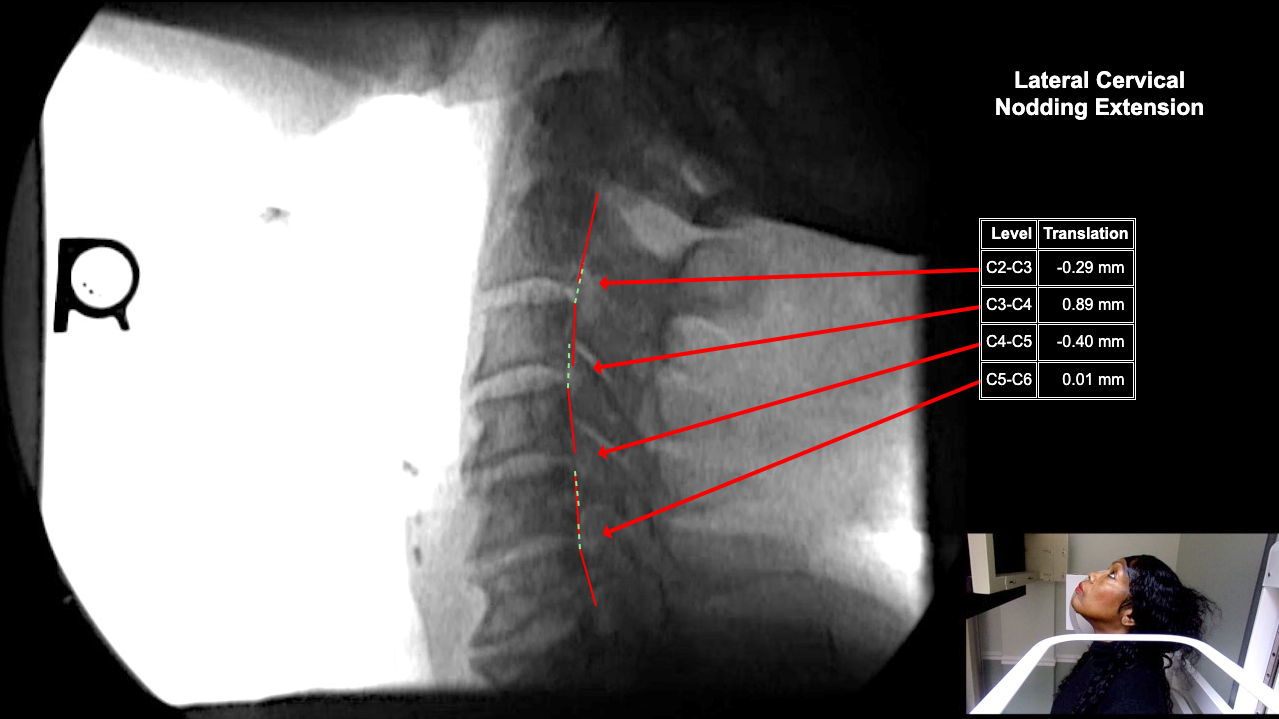

Home > Catherine Basseck 10-23-25